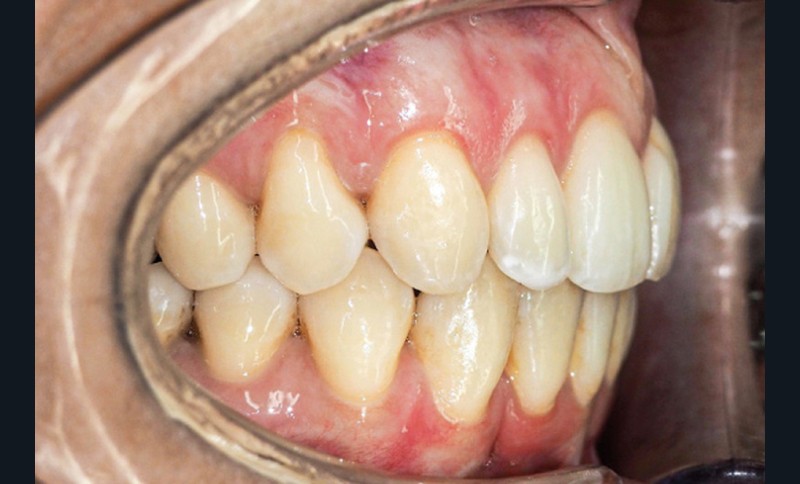

Examen endo-buccal (fig. 2a-e)

En occlusion, on note une relation de Classe I molaire bilatérale avec un surplomb normal et une supraclusion. Les médianes incisives sont concordantes.

Les incisives maxillaires sont de forme triangulaire [1] et l’indice de Bolton est de 97 % qui traduit la présence d’une DDD par excès mandibulaire.